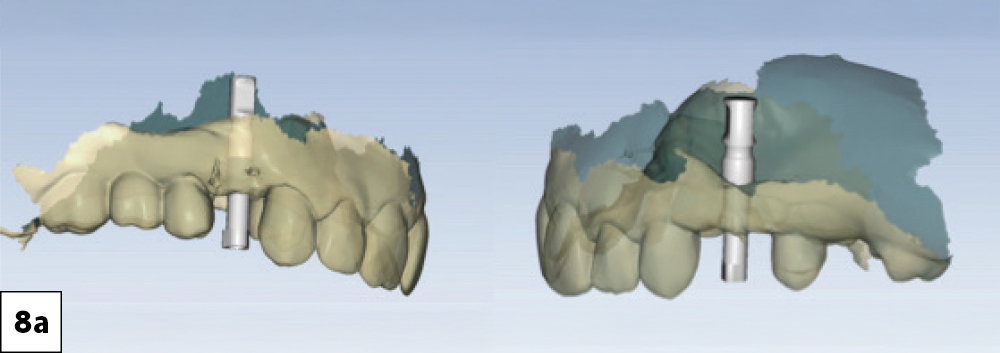

The fastdesign.io software automatically recognized the implant platforms and the geometry of the BruxZir® NOW SRC zirconia milling blocks prefabricated with attached titanium bases

This new milling block design represents a significant leap forward in chairside implant restoration

Figures 8a, 8b: The fastdesign.io software automatically recognized the implant platforms and the geometry of the BruxZir® NOW SRC zirconia milling blocks prefabricated with attached titanium bases. This new milling block design represents a significant leap forward in chairside implant restoration. Traditionally, milled zirconia restorations require a secondary bonding step in which the crown is luted to a separate titanium base after milling. This added complexity introduces potential for misalignment and creates a junction that can weaken over time if not executed perfectly. By contrast, the new BruxZir NOW SRC zirconia blocks integrate the Ti-base directly into the milling blank at the manufacturing stage, creating a monolithic restorative unit with a precise, factory-verified interface. This eliminates bonding errors, ensures consistent torque stability, and allows the restoration to be seated immediately after milling with exceptional fit.